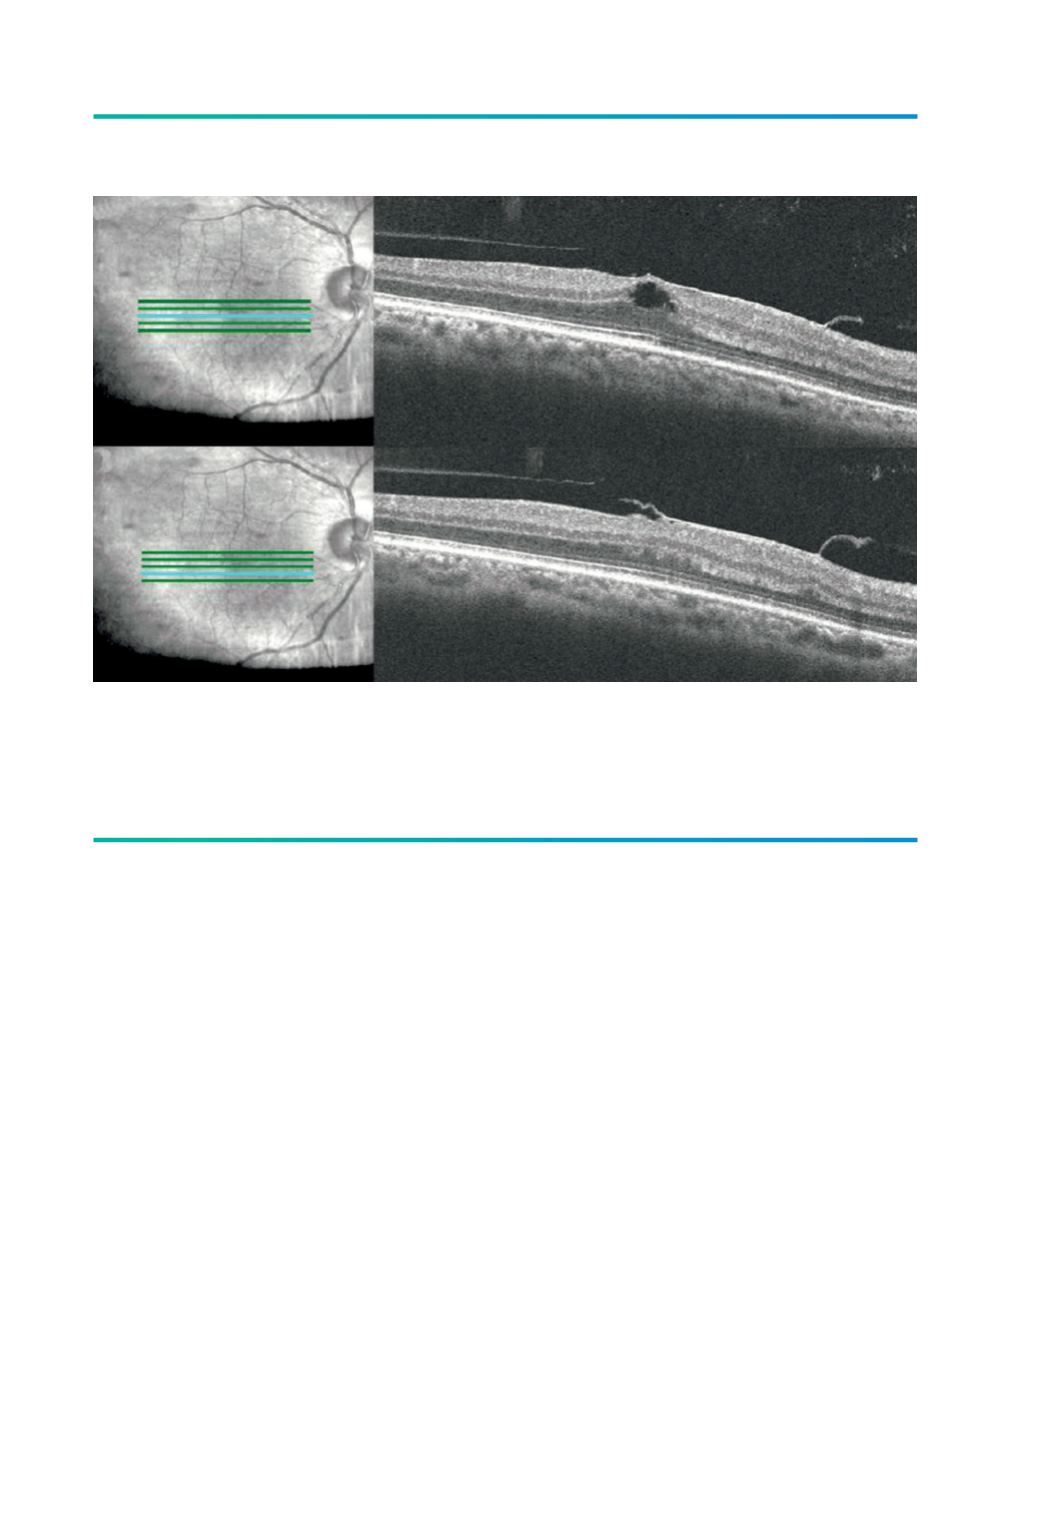

Figura 1.

TVM alargada isolada. Imagem de refletância com luz infravermelha demonstra a orientação do corte

tomográfico (A e C). O estudo por SD-OCT mostra (B) descolamento posterior do vítreo (DPV) perifoveal

com adesão vítreo-macular alargada, rectificação da depressão foveal e um quisto intra-retiniano e (D) DPV

perifoveal com adesão alargada e distorção da superfície retiniana (Imagens: cortesia de Nuno Gomes).

A

C

D

B